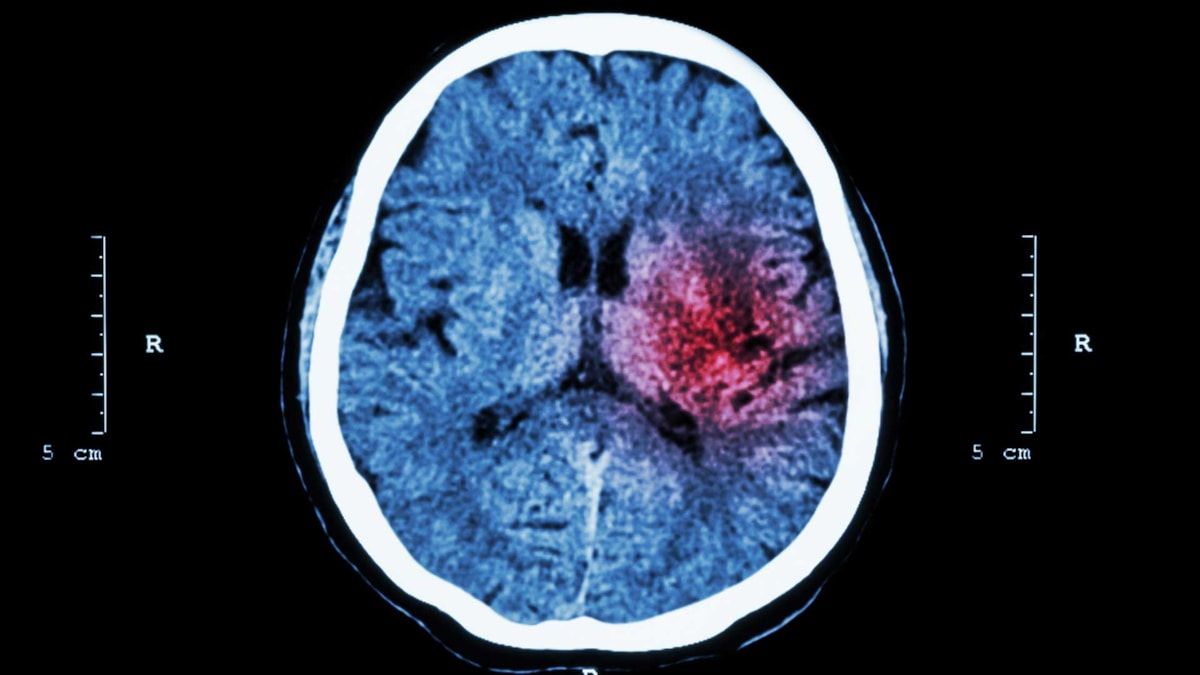

Behandling og utredning ved hjerneslag

For å behandle hjerneslaget må en skille mellom hjerneinfarkt og hjerneblødning. Da må det tas CT- eller MR-bilde av hodet. Vanligst er det å ta et CT-bilde først. Dette gjøres raskt etter innleggelse i sykehus. En blodpropp ses ikke alltid på de første bildene, mens en blødning ses ofte umiddelbart.